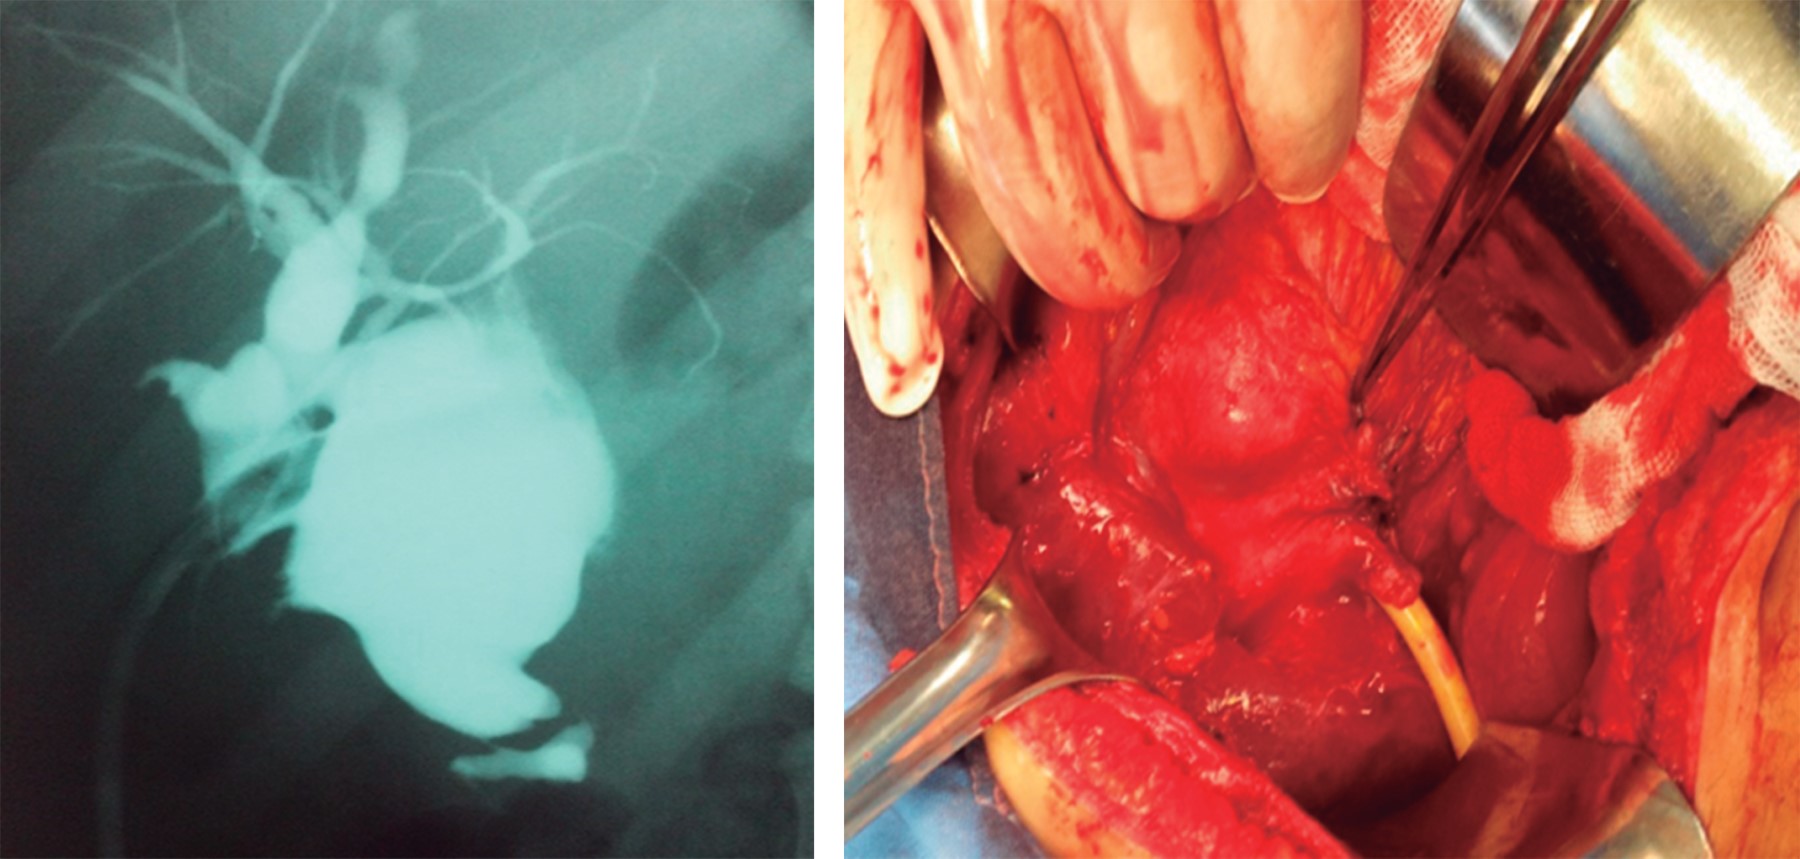

Caso clínico 1: femenino de 14 años, cuatro años de evolución con dolor tipo cólico en hipocondrio derecho. Cuatro meses previos a su ingreso presentó episodios más frecuentes, agregándose ictericia, coluria, acolia, náuseas y vómito. Ingresó con ictericia, dolor a la palpación en hipocondrio derecho y epigastrio, y una tumoración de aproximadamente 15 × 15 cm. Las pruebas de función hepática mostraron hiperbilirrubinemia mixta (bilirrubina total: 7.1 mg/dl, bilirrubina directa: 3.7 mg/dl, aumento de la fosfatasa alcalina: 651 U/l). El ultrasonido reveló colecistitis litiásica, coledocolitiasis versus quiste de colédoco; la tomografía axial computarizada: colecistitis litiásica y dilatación quística de la vía biliar (Figura 1). La colangiorresonancia mostró un quiste de colédoco de 72 mm con dilatación de la vía biliar intrahepática (Figura 2). Se realizó cirugía electiva, se encontró vesícula biliar con litos y un quiste de colédoco tipo I de la clasificación de Todani adherido a duodeno de 17 × 10 × 10 cm (Figura 3).

Caso clínico 2: mujer de 43 años, con dolor tipo cólico en hipocondrio derecho, sin síntomas acompañantes, acudió a un hospital rural, donde se le realizó colecistectomía abierta durante la cual se observó aumento del diámetro del colédoco. Se decidió efectuar coledocotomía con colocación de sonda en T. En la consulta externa se solicitó colangiografía por sonda en T, ésta reportó un quiste de colédoco, por lo que fue referida a nuestro hospital. Ingresó sin ictericia y sonda tipo Kerr abierta con gasto biliar. Las pruebas de función hepática dentro de parámetros normales sólo registraron hipoalbuminemia. Se realizó cirugía con hallazgos de quiste de colédoco de 15 × 8 × 7 cm adherido a duodeno, estómago, páncreas, vena porta y vena cava; conducto hepático derecho e izquierdo con diámetro de 1 cm.

Caso clínico 3: femenino de 15 años, con historia de dolor en hipocondrio derecho y fiebre; el ultrasonido reveló absceso hepático. Se sometió a laparotomía exploradora donde se encontró quiste gigante de colédoco a tensión con necrosis y adherencias hacia vesícula. Se realizó coledocotomía, aspiración y cierre primario con colocación de drenaje tipo Penrose. Al segundo día del postoperatorio se registró salida de 400 cm3 de bilis a través del drenaje y, mediante ultrasonido, líquido libre en cavidad, motivo por el que fue sometida a nueva laparotomía; se realizó drenaje, colecistectomía y colocación de sonda Kerr en bolsa de quiste. Fue referida a nuestro hospital, donde se mantuvo con tratamiento médico y posteriormente fue enviada a consulta externa. La colangiografía por sonda en T reveló bolsa quística compatible con quiste de colédoco. Se llevó a cabo cirugía programada, se detectó quiste de colédoco de aproximadamente 8 × 5 cm con sonda en t en su interior y múltiples adherencias (Figura 4).

Figura 3

Figura 4